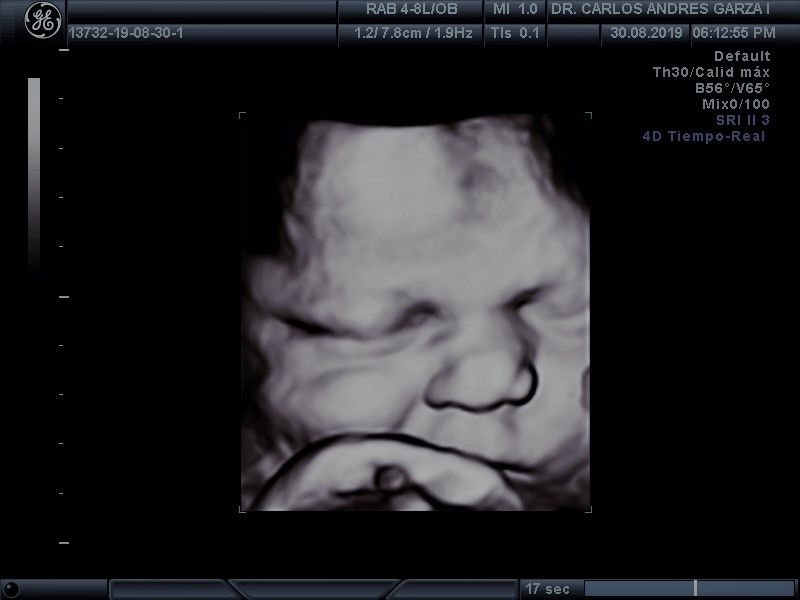

Ultrasonido 4D

!Conoce a tu bebé hoy¡ Se trata de la última tecnología en ecografía o ultrasonido a nivel mundial, que consiste en un procesamiento de reconstrucción digital de imágenes para formar una sola imagen en 4 dimensiones, permitiendo así poder visualizar cualquier estructura tal cual la estuviésemos viendo directamente el rostro de tu bebé, antes de nacer. Con esta nueva generación de tecnología del ultrasonido puedes observar datos mas detallados de su bebé, sus movimientos, gestos, risas, bostezo, etc... tal como si lo tuviera en sus brazos. En el pasado los papas no conocían la cara de su bebe hasta que naciera.

Asistencia y control al parto

Llevamos el control de tu embarazo hasta el término del mismo, con la mejor tecnología en cuanto se refiere al ultrasonido 4D, que nos permite revisar de una mejor manera a tu bebé, atendiendo parto o cesárea en los hospitales de la región.